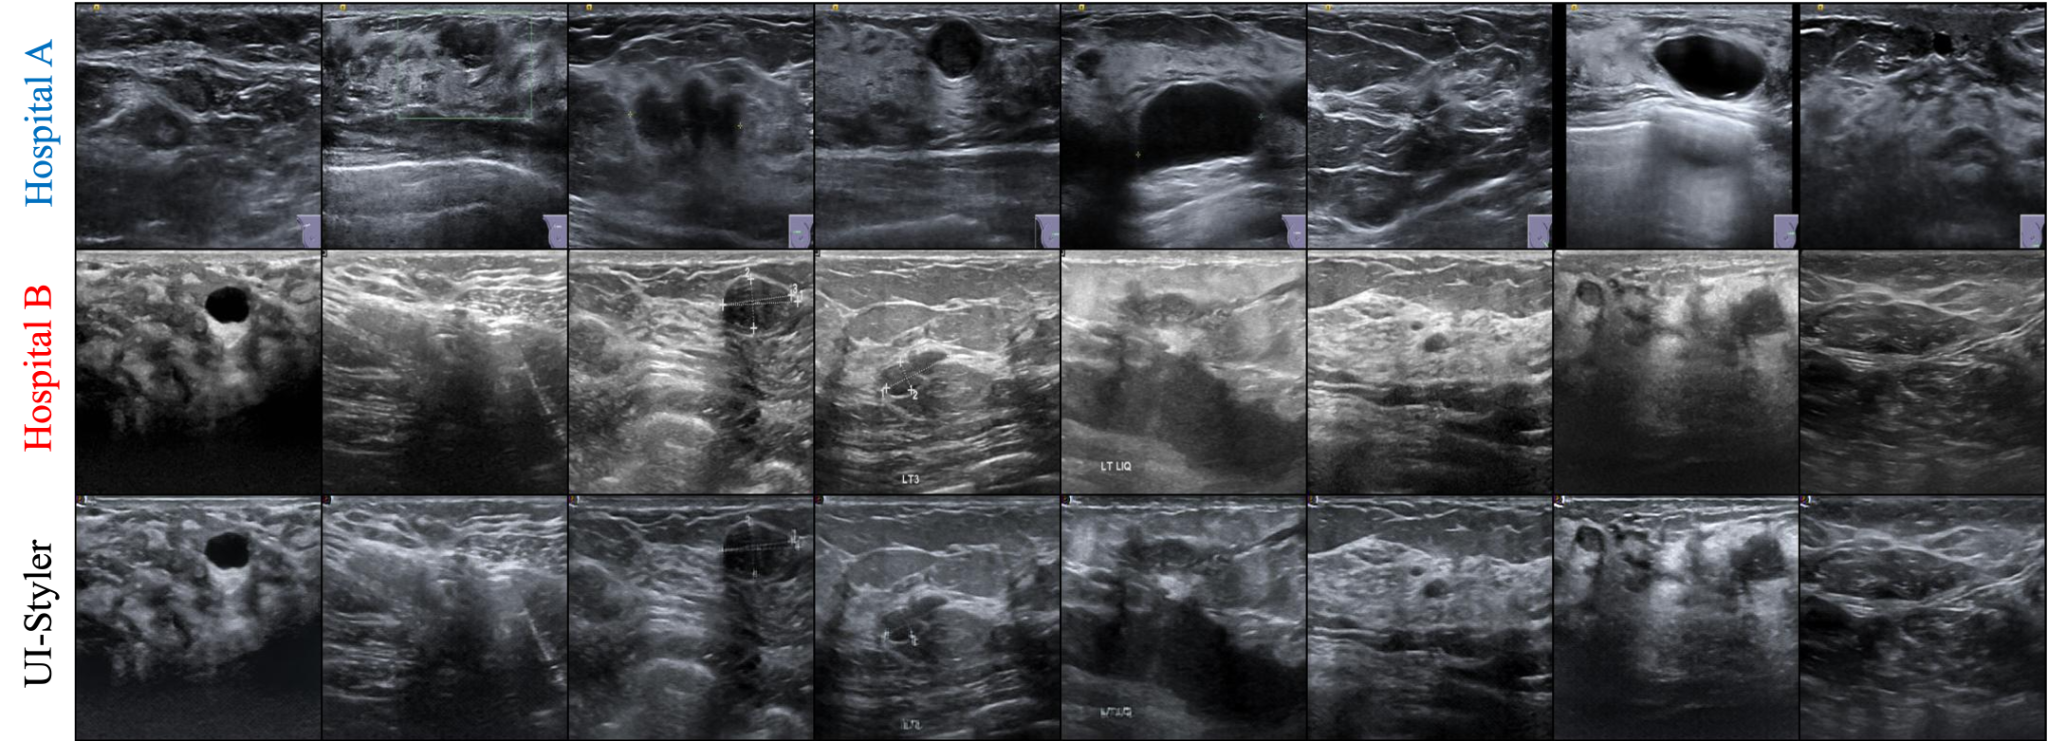

🖼️ Visual Results